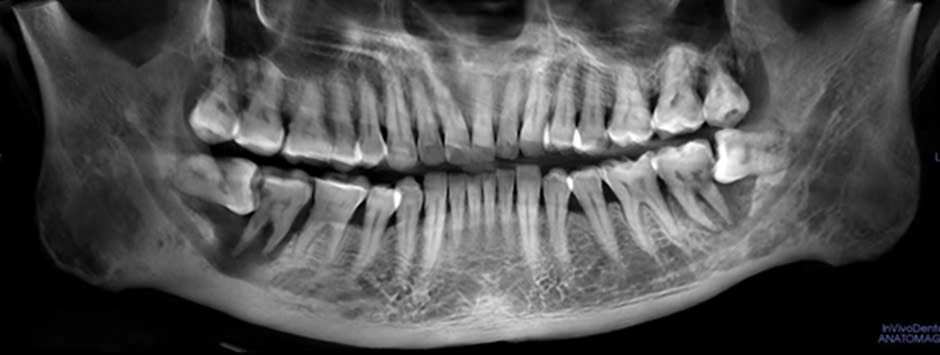

Răng khôn (răng số tám hay răng hàm lớn thứ ba) là răng mọc cuối cùng, thường mọc ở độ tuổi trưởng thành từ 18 đến 25 tuổi. Đây là răng hay gây nhiều biến chứng nhất trên cung hàm. Trong quá trình mọc và suốt thời gian tồn tại, răng khôn gây ra rất …